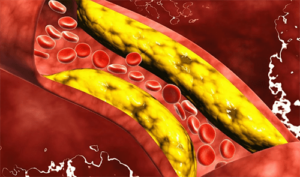

Jenis pertama diwakili oleh lipoprotein densitas tinggi, yang mencegah kontaminasi pembuluh darah dengan endapan asing. “Kolesterol jahat” mengacu pada lipoprotein densitas rendah yang dapat mengendap di dasar pembuluh darah dan menimbulkan masalah kesehatan.

Ada juga berbagai lipoprotein densitas sangat rendah. Peningkatan kolesterol jahat dalam darah, apa artinya? Setelah terbentuk, plak tidak hilang dari tubuh di mana pun. Dengan menyumbat arteri, itu mencegah lewatnya darah dan oksigen ke organ dalam.

Secara bertahap, lumen pembuluh menyempit, aterosklerosis sering didiagnosis pada usia muda.